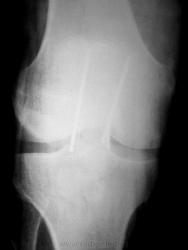

Пол пациента: Мужской пол Тип патологии: Травма Область исследования: Скелетно-мышечная система Методы исследования: Rg После операции. И так бывает, пациент жалоб не предъявляет https://radiomed.ru/sites/default/files/styles/case_slider_image/public/user/6152/2000.jpg?itok=kpUbJZyq https://radiomed.ru/sites/default/files/styles/case_slider_image/public/user/6152/2002.jpg?itok=ekIs4rwy https://radiomed.ru/sites/default/files/styles/case_slider_image/public/user/6152/2003.jpg?itok=G7ZQHQ9V ID:7928 Втр, 12/10/2010 - 14:10 #1 Александр Викторович Не на сайте Был на сайте: 8 лет 2 дня назад Зарегистрирован: 31.07.2010 - 13:05 Публикации: 639 летать будет проблематично, в смысле авиаперелетов... Втр, 12/10/2010 - 20:53 #2 stovbav Не на сайте Был на сайте: 2 года 2 месяцев назад Зарегистрирован: 20.12.2009 - 17:28 Публикации: 7066 Раз жизнь "обломала" то и травматологи не стали ей перечить, пошли тем же путем, да, очевидно, и правильно сделали. Болезни ног: виды, симптомы, причины, профилактика и лечение